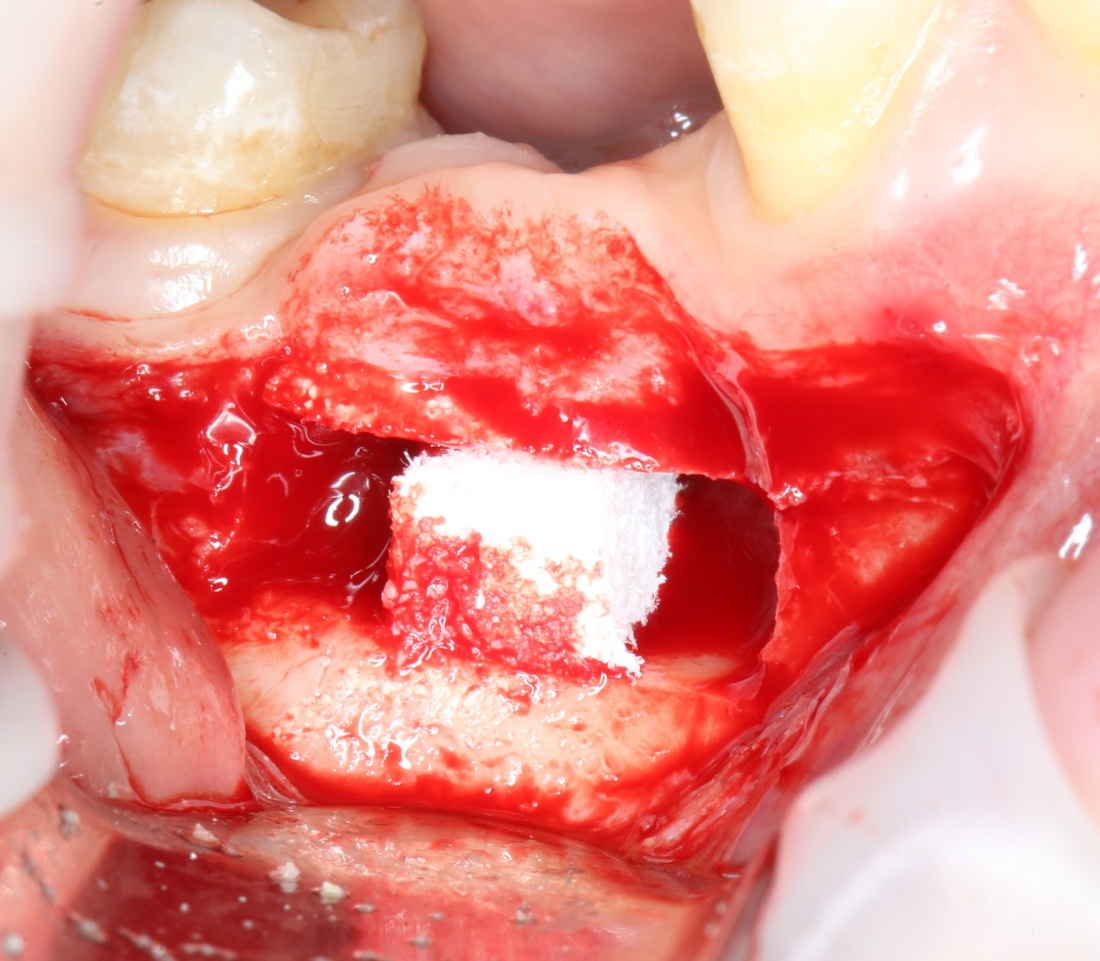

Результат остеопластики методом остетотомии мы можем оценить уже через 4 месяца. Перед этим сделаем контрольные снимки (слева «до», справа «через 4 мес»):

Откроем область операции и посмотрим, что там:

Вроде как, всё неплохо. Наверное, можно поставить имплантаты?

ну, или как-то так:

При этом, я хотел бы обратить ваше внимание на один важный момент. То, с чем вы сейчас работаете — не кость, в привычном нам гистолого-физиологическом понимании. Это костная мозоль вперемежку с графтом. Её свойства довольно сильно отличаются от того, что мы привыкли называть костной тканью. Поэтому при установке имплантатов соблюдайте максимальную осторожность и щадящий режим. Никаких диких торков, усилий, больших переходов между размерами фрез допускать нельзя. Будьте аккуратны.

Иначе, кривокосячной имплантацией вы можете испортить даже мастерски проведенную остеопластическую операцию.